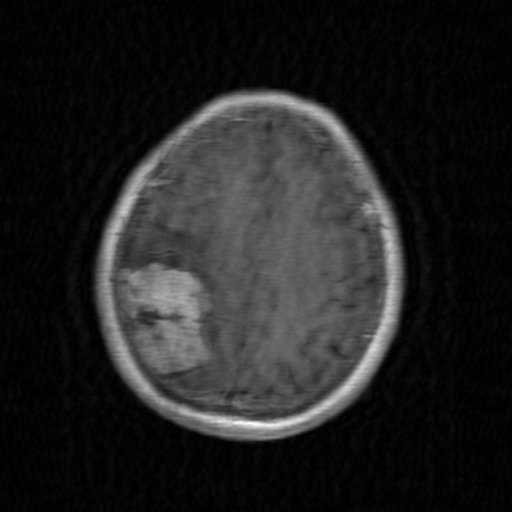

MRI 伪影场景下的 PSNR 分析

-

30 dB 结果

- 意义:表示生成的伪影图像与原始图像的差异处于合理范围,伪影可见但未完全破坏结构。

- 典型场景:

- 运动伪影:25-35 dB

- 欠采样伪影:28-38 dB

-

与其他指标的对比

- SSIM > 0.9:结构相似性高(30 dB PSNR 通常对应 SSIM 0.85-0.95)

- 视觉评估:30 dB 时伪影可能肉眼可见但可接受(如下图):